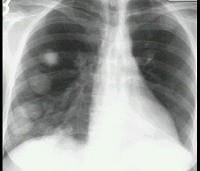

女,48岁,胸痛1周,结合影像图像选择最可能的诊断为 ( )A.肺转移瘤B.韦格肉芽肿C.肺类风湿病D.多发性肺脓肿E.肺癌

问题 女,48岁,胸痛1周,结合影像图像选择最可能的诊断为 ( )

选项 A.肺转移瘤 B.韦格肉芽肿 C.肺类风湿病 D.多发性肺脓肿 E.肺癌

答案 A